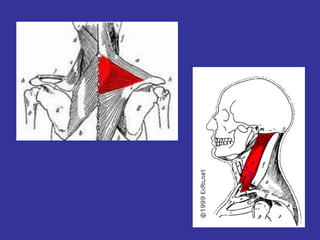

Nervo acessório (XI par)

XI – NERVO ACESSÓRIO

• Formado por uma raiz craniana (bulbar) e

raiz espinhal (filamentos radiculares –

emergem da face lateral dos 5 ou 6

primeiros segmentos cervicais da medula

que penetra no crânio pelo forame magno)

• Craniana+espinhal forame da jugular